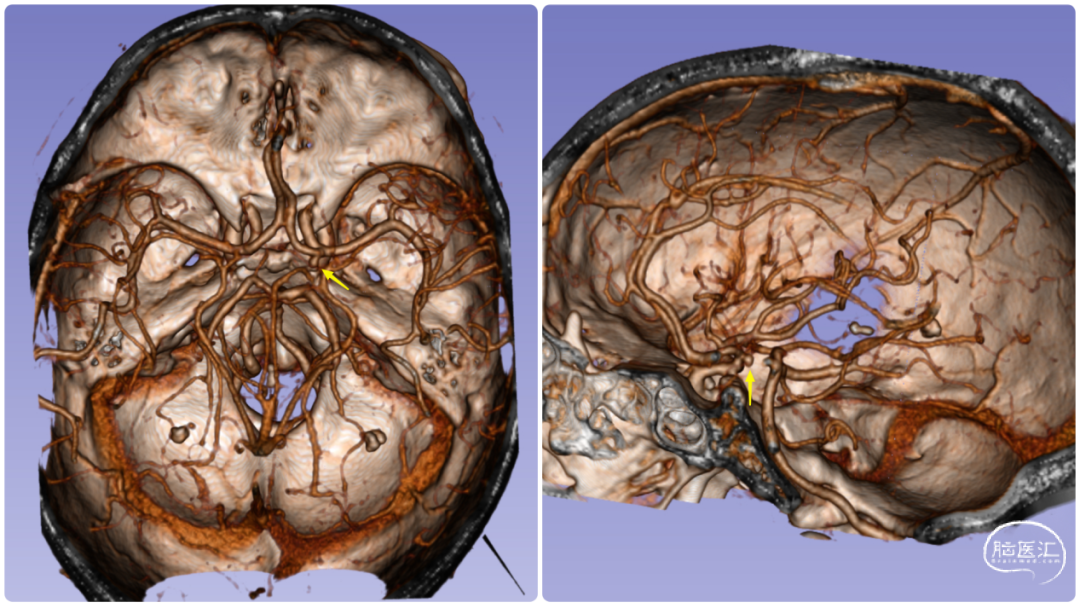

图3. DSA模拟手术体位

1. 右侧A1近端动脉瘤破裂伴蛛网膜下腔出血明确,该部位动脉瘤发病率低,目前检查首先考虑为真性动脉瘤,治疗可选择血管内介入治疗,也可选择开颅夹闭动脉瘤。

2. 该部位动脉瘤介入在微导管超选中难度系数高,对微导管塑形要求高,且术中微导管稳定性差,易踢管。

3. 若选择开颅夹闭,动脉瘤藏于额叶后方,需将侧裂彻底分离,进行阻断后夹闭,需注意细小分支避免损伤。经与患者及家属充分沟通后,患者要求行开颅手术夹闭治疗。